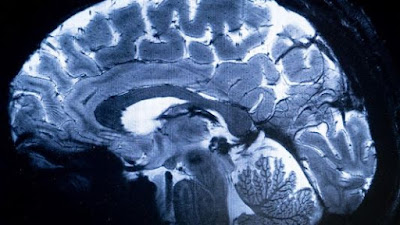

ફ્રેન્ચ વૈજ્ઞાનિકોએ વિશ્વના સૌથી શક્તિશાળી મેગ્નેટિક રેઝોનન્સ ઇમેજિંગ (MRI) સ્કેનરમાં મગજનું સ્કેનિંગ કરવામાં આવ્યું.

• આ સ્કેનર દ્વારા માનવ મગજની અત્યાર સુધીની સૌથી સચોટ અને ઉચ્ચ ગુણવત્તાવાળી ઇમેજ બનાવવામાં આવી છે.

• આ નવા MRI સ્કેનર મશીનની ક્ષમતા 11.7 ટેસ્લા છે.

• આ મશીન મગજના સેરેબ્રલ કોર્ટેક્સ સુધી પહોંચતી નાની રક્તવાહિનીઓ પણ જોઈ શકે છે.

• તેની મદદથી મગજમાં સેરેબેલમ પણ સારી રીતે જોઈ શકાય છે.

World’s most powerful MRI scans first images of human brain